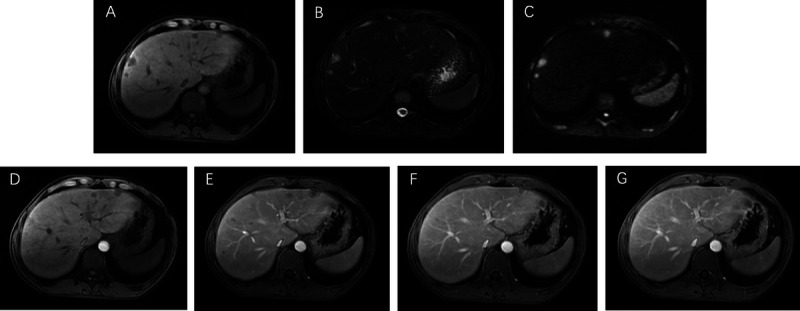

Abstract Image